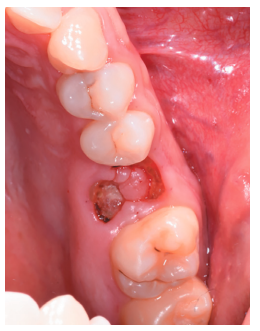

Caso clínico: se presenta el caso de un varón de 28 años, que acudió a consulta por la presencia de unos restos radiculares en localización de primer molar superior izquierdo. Se realizó un autotrasplante dental, siendo el diente donante el tercer molar superior izquierdo, que se trasplantó al alveolo del primer molar, mostrando buena evolución clínica y radiográfi ca.

Clinical case: a clinical case of a 28-yearold man is presented, who went to dental clinic for removal of left fi rst molar roots. An autotransplant was performed using left third molar as donor tooth, which was transplanted into fi rst molar alveolus, showing promising clinical and radiographic evolution.